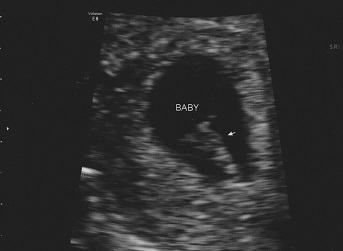

Here's our little dude! DH looked like he was going to pass out when he saw this. It was cracking me up. I guess no amount of time waiting and hoping for it actually prepares you for the shock of it being real! Doc says the baby is moving a ton and that I'm in for quite a ride if dude's moving that much at 8 months. WOOHOO!